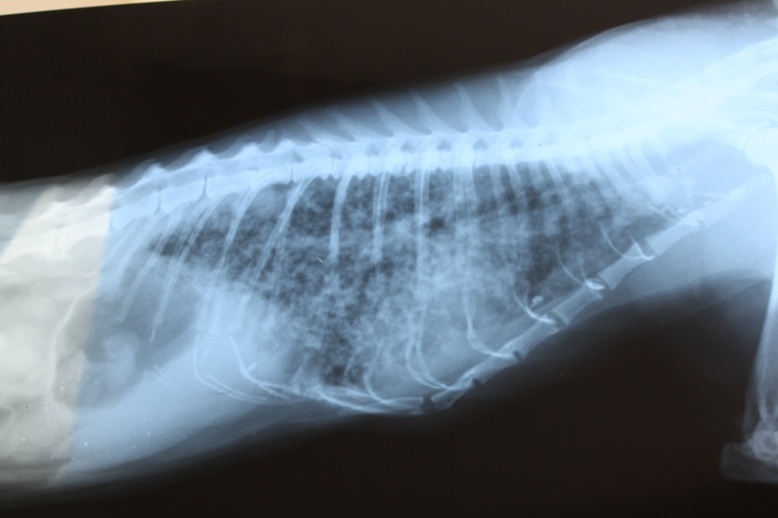

вижу его любимое место,сижу и начинаю реветь.Мне 15 лет мальчик,но все равно не могу никак сдержать слезы.Смотрю на фотографии,плачу 3 дня немогу прийти в себя.Жил с нами 8 практически 9 лет,взяли на улице одинокого,маленького котёнка с 2-го класса я с ним неразрулимы.Постоянно приходил со школы,он прибегал начинал мурлыкать,мяукать,и тут сразу бросал портфель и 2 часа непрерывно с ним игрались.У него была мочекаменная болезнь,ходили по вет лечебницам хоть антибиотики ставить,они блин не знаю как их назвать,не делают етого.Зачем спрашивается становиться ветеринаром если ничего не умеет?Котетор не хотел ставить,не хотел видеть как он мучается с котетором,ето была бы не жизнь.1 раз мочекаменная болезнь отступила,2 тоже,а вот на 3-ий раз он мучался ужасно,за ето я себя виню.2 дня лежал просто не шевелясь,я ему давал таблетки через шприц(без иглы)но болезнь не отступала,как я думал в другие разы всё пройдёт.Потом на 3-ий ето в четверг было мы решились поехать в город,чтобы там что-то врачи посоветовали,но как только мы отъехали,он так посмотрел на меня,вздохнул последний раз и умер,в машине.Если бы я знал я бы лучше его дома оставил чтобы он умер хотя бы в родном месте.Потом мы вернулись я дико плакал,хоть ниразу в жизнь никогда не плакал.Если бы мы раньше хоть на миг успели,я молил Бога чтобы он дал ему жизнь,но всёравно он погиб.Сейчас каждый раз убираю лоток куда он ходил,налил ему воды,несу с улицы травы,хоть знаю что он умер.Мне кажется что он где-то рядом.Я постоянно смотрю на кровать,где он лежал на против меня,смотрю на балкон откуда он постоянно выбегал,смотрю фотографии и не могу ничего сказать.Если бы я только знал,я бы ему все самые теплые слова сказал,я бы его обнял,поцеловал,но я опоздал.Когда он умер я тогда понял что немогу больше ему ничего сказать,не обнять,ни поцеловать,ни сказать как сильно я его любил и люблю сейчас.Я его похоронил в 1 день,каждый день хожу на могилку в лес.Я надеюсь что действительно Мост Радуги существует,что ему там хорошо,что у него много новых друзей,и его болезнь исцелилась.Я веню себя за то что не смог дать ему всю свою любовь,я был слеп,думал что всё пройдёт.Я с ним не попрощался